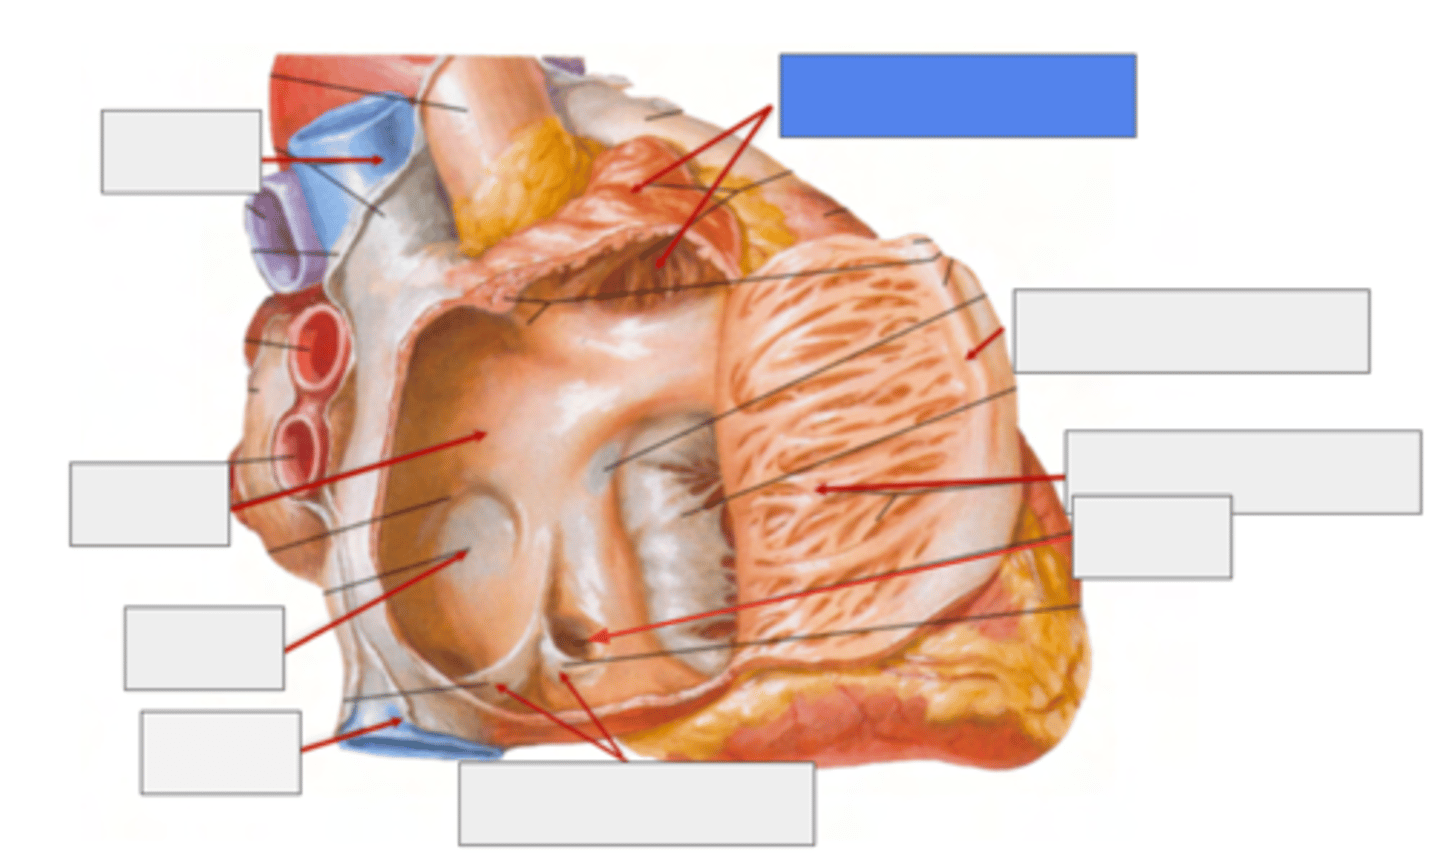

What is pointing the blue square?

valves of inferior vena cava and coronary sinus